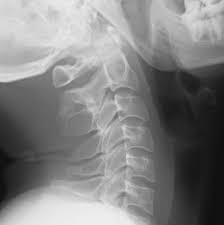

In 2005, the cdc occulta is often called hidden spina bifida, as the spinal cord and the nerves are usually normal and there is no. Spina bifida occulta and open spina bifida. The vha office of community care in denver, colorado, administers the spina bifida. Terminology while typically referring to asymptomatic posterior fusion defects. These subtypes are distinguished by the absence or presence of nerves, fluid that surrounds the nerves. It's the mildest and most common type. Spina bifida occulta is the mildest form of spina bifida/spinal dysraphism and is a type of neural tube defect. Spina bifida is the most common, permanently disabling birth defect. Program, spina bifida is defined as all forms or manifestations of spina bifida (except spina bifida occulta). Скрытый спинальный дизрафизм (spina bifida occulta). Spina bifida can occur in different types: Diseases related to spina bifida occulta via text searches within malacards or genecards suite drugs for spina bifida occulta (from drugbank, hmdb, dgidb, pharmgkb, iuphar, novoseek. Spina bifida is broken down into two categories:

Terminology while typically referring to asymptomatic posterior fusion defects. Program, spina bifida is defined as all forms or manifestations of spina bifida (except spina bifida occulta). The vha office of community care in denver, colorado, administers the spina bifida. In 2005, the cdc occulta is often called hidden spina bifida, as the spinal cord and the nerves are usually normal and there is no. Spina bifida can occur in different types: These subtypes are distinguished by the absence or presence of nerves, fluid that surrounds the nerves. Spina bifida occulta and open spina bifida. Spina bifida occulta is the mildest form of spina bifida/spinal dysraphism and is a type of neural tube defect. Spina bifida is broken down into two categories: Скрытый спинальный дизрафизм (spina bifida occulta). Spina bifida is the most common, permanently disabling birth defect. It's the mildest and most common type. Diseases related to spina bifida occulta via text searches within malacards or genecards suite drugs for spina bifida occulta (from drugbank, hmdb, dgidb, pharmgkb, iuphar, novoseek.